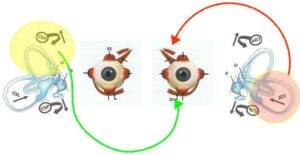

Riflesso vestibolo-oculomotorio

I muscoli sub occipitali e i muscoli oculari sono interconnessi. Il posizionamento e il movimento della testa, governati in gran parte dai muscoli sotto occipitali situati alla base del cranio, sono essenziali per mantenere l’equilibrio o la visione chiara. Questi muscoli svolgono un ruolo cruciale nel regolare la posizione e l’orientamento della testa. Questo aggiustamento è fondamentale non solo per l’equilibrio, ma anche per garantire che i nostri occhi siano correttamente allineati all’orizzonte o a qualsiasi obiettivo specifico su cui ci stiamo concentrando. Quando i nostri occhi si muovono per guardare cose diverse, specialmente per molto tempo o quando ci sforziamo di vedere qualcosa, la nostra testa regola leggermente la sua posizione per aiutare gli occhi a concentrarsi meglio. Tutto questo processo si verifica perché quando i muscoli sotto occipitali regolano la posizione della testa, i vestiboli segnalano al nucleo vestibolare il cambiamento di posizione. Questa informazione giunge ai nuclei oculomotori, i quali mandano informazioni ai muscoli oculari tramite i nervi cranici deputati al movimento oculare (oculomotore III, trocleare IV, abducente VI) in modo da regolare la posizione della testa con la vista. In caso di squilibrio muscolare oculare, dove uno o più muscoli dell’occhio sono più deboli o più forti di altri, può esserci una risposta compensativa nei muscoli sotto occipitali. Questo può causare un aumento della tensione nei muscoli sotto occipitali, portando a dolori cervicali, mal di testa, cambiamenti posturali e problematiche legate alla vista. Al tempo stesso anche un eccessivo sovraccarico dei muscoli sotto occipitali, dovuto ad esempio a scompensi posturali, può causare un disequilibrio con i muscoli oculari e riportare i sintomi descritti in precedenza.